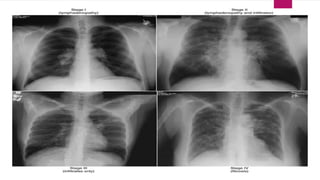

 By convention thoracic sarcoidosis is classified in four (04) stages on the basis

 Stage I:Represents bilateral hilar lymphadenopathy

 Stage II: Bilateral adenopathy plus pulmonary opacities

 Stage III: Pulmonary opacities only

 Stage IV: Represents the development of irreversible pulmonary fibrosis

Stage II is BHL and infiltrates

Stage III is infiltrates alone